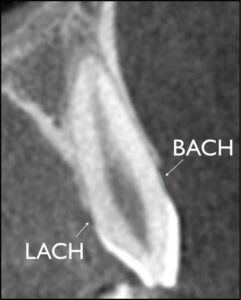

In the frontal and sagittal images, an axial section passing through the trifurcation of the right first permanent molar was selected. On this image, the buccal and lingual alveolar bone thicknesses were measured on the C3 and on the NC3 and NC2 (Fig 2). The buccal and lingual alveolar crest heights were measured on cross sections passing through the center of the crowns of the C3, NC3, and NC2, with the cementoenamel junction (CEJ) as a reference (Fig 3).

Fig 3. Measurement of buccal and lingual alveolar crest heights.